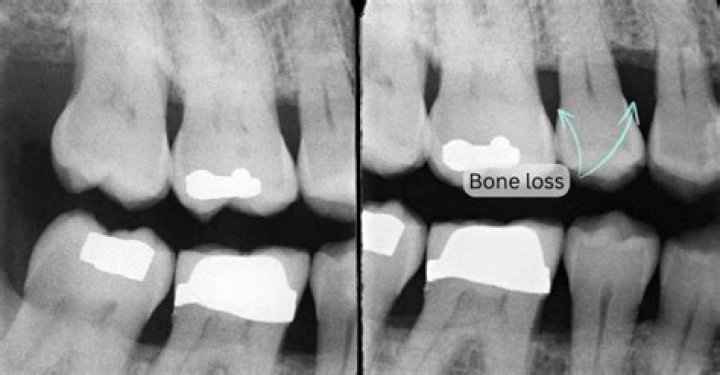

Can you see bone loss on an X-ray?

However, x-rays are note used to diagnose osteoporosis. X-rays can only detect bone loss after 25-40 percent of the skeleton has been depleted and should not be used to identify the presence of osteoporosis.